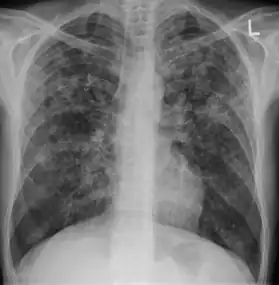

7. Other - Any other finding suggestive of active TB, such as miliary TB. Miliary findings are nodules of millet size (1 to 2 millimeters) distributed throughout the parenchyma.